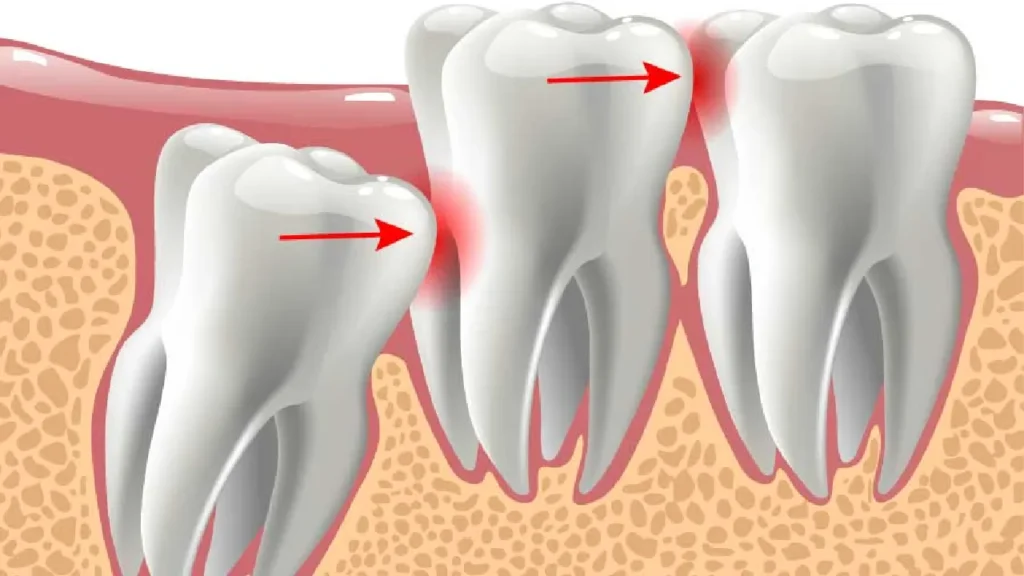

Most mouths do not have enough room to accommodate the wisdom teeth, also known as third molars. As a result, they may become impacted, meaning they cannot fully emerge from the gums. Impacted wisdom teeth can lead to severe pain and, infection, and damage to adjacent teeth.

The presence of wisdom teeth can exert pressure on the existing teeth, causing them to become misaligned or crowded. This can negatively affect the alignment of other teeth and last adult teeth in your smile and may require orthodontic treatment to correct.

In some cases, the sac surrounding exposed bone of an impacted wisdom teeth or wisdom teeth extraction or tooth can develop fluid-filled cysts or, rarely, tumors. These can cause damage to the surrounding bone of impacted wisdom teeth and neighboring teeth if left untreated.